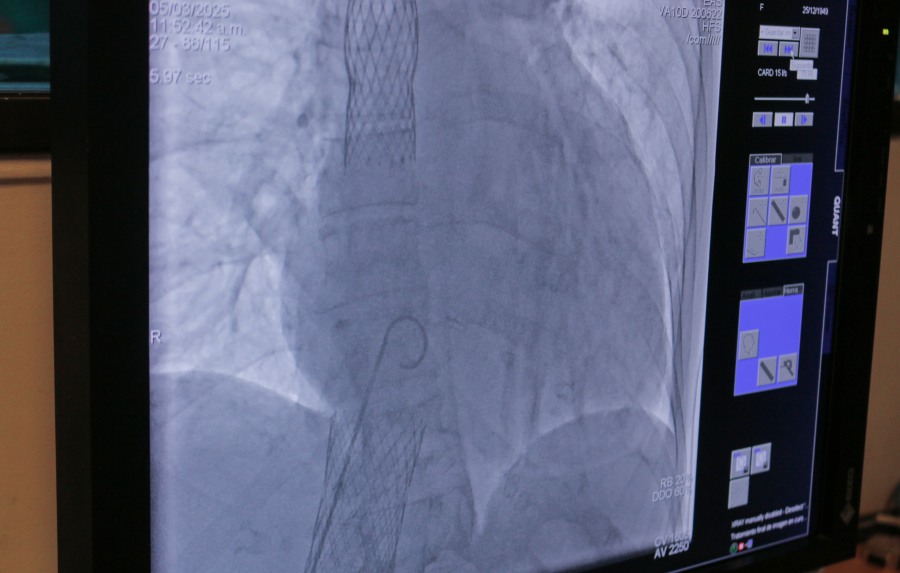

Desde el Servicio de Hemodinamia del Hospital Escuela de Agudos Dr. Ramón Madariaga, el Dr. Ernesto Duarte contó cómo se llevó a cabo esta innovadora cirugía que consiste en la colocación de una válvula aórtica en las venas cavas superior e inferior del corazón del paciente.

Este tipo de intervención está especialmente indicada para aquellos que sufren de insuficiencia cardíaca y que han enfrentado múltiples internaciones, con el objetivo de reducir la tasa de hospitalización y mejorar la calidad de vida del paciente.

La insuficiencia tricuspide, una patología a menudo olvidada, presenta una alta mortalidad quirúrgica, lo que hace que este procedimiento sea aún más valioso, ya que la mortalidad asociada al implante de esta válvula es inferior al 1%.

El Dr. Enzo Moreschi, también parte del equipo médico, destacó que el Hospital está realizando estudios sobre la válvula aórtica sin necesidad de cirugía convencional, lo que significa que no se requiere abrir el pecho del paciente.

“Este enfoque endovascular permite que los pacientes se beneficien de un procedimiento menos invasivo, con un tiempo de recuperación mucho más rápido”, añadió.